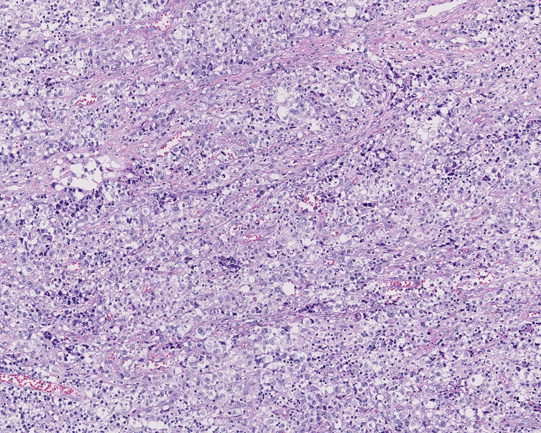

20歳 鼠径リンパ節

左臀部の痛みで発症する。臀部軟部組織に腫瘤を認めCTで腸骨, 大腿骨の欠損あり。左鼠径, 大動脈周囲, 後腹膜, 骨盤内腔のリンパ節が腫大し脾腫、胸水腹水の貯留を認める。WBC 15500/cmm, LDH 470(<350), sIL2-R29100U/ml

リンパ節組織所見

大型異型細胞が集簇し結合性に増殖している。未分化癌や悪性黒色腫が鑑別となる。細胞は大型で類円形, 楕円形核に加えて腎臓様の特異な核形を示す。

免疫染色:CD3-, CD4-, CD8-, CD15-, CD20-, CD30+, CD43-, CD45RO-, CD56-, TIA1+, granzymeB+, ALK+, EMA+, EBER-ISH-, LMP1-, BCL2- (以上, consultation先で染色)

Pathological Diagnosis: ALK-positive anaplastic large cell lymphoma